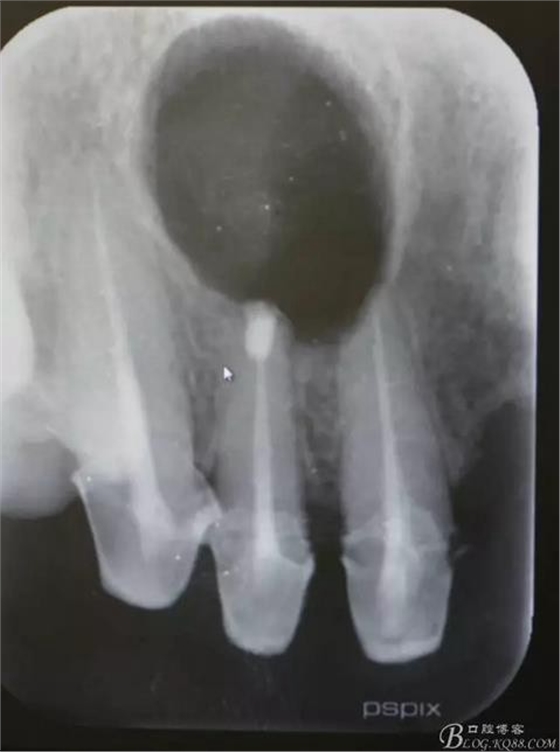

患者、王xx、女、56歲。主訴:右側(cè)上顎部反復(fù)腫痛兩年。??茩z查:上半口烤瓷橋修復(fù),12腭側(cè)隆起,捫診有輕微觸痛。X光:12根尖有圓形規(guī)則陰影,范圍月、約1.0x1.2cm,邊界清晰,11、12根管治療不完善。診斷:12根尖囊腫。治療計(jì)劃:1.行11、12根管治療術(shù)。2.擇期行根尖手術(shù)?;颊咄庵委煼桨?,簽知情同意書。

圖1.術(shù)前的根尖片影像檢查:11、12根管治療不完善